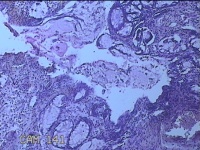

性别

男

年龄

40岁

临床诊断

混合痔

一般病史

反复肛门肿物突出15年。

标本名称

肛门肿物

大体所见

灰白暗红色肿物0.7x0.5x0.2cm一个,表面糜烂。

脱水、透明,浸蜡、脱蜡效果不佳,制片质量差。